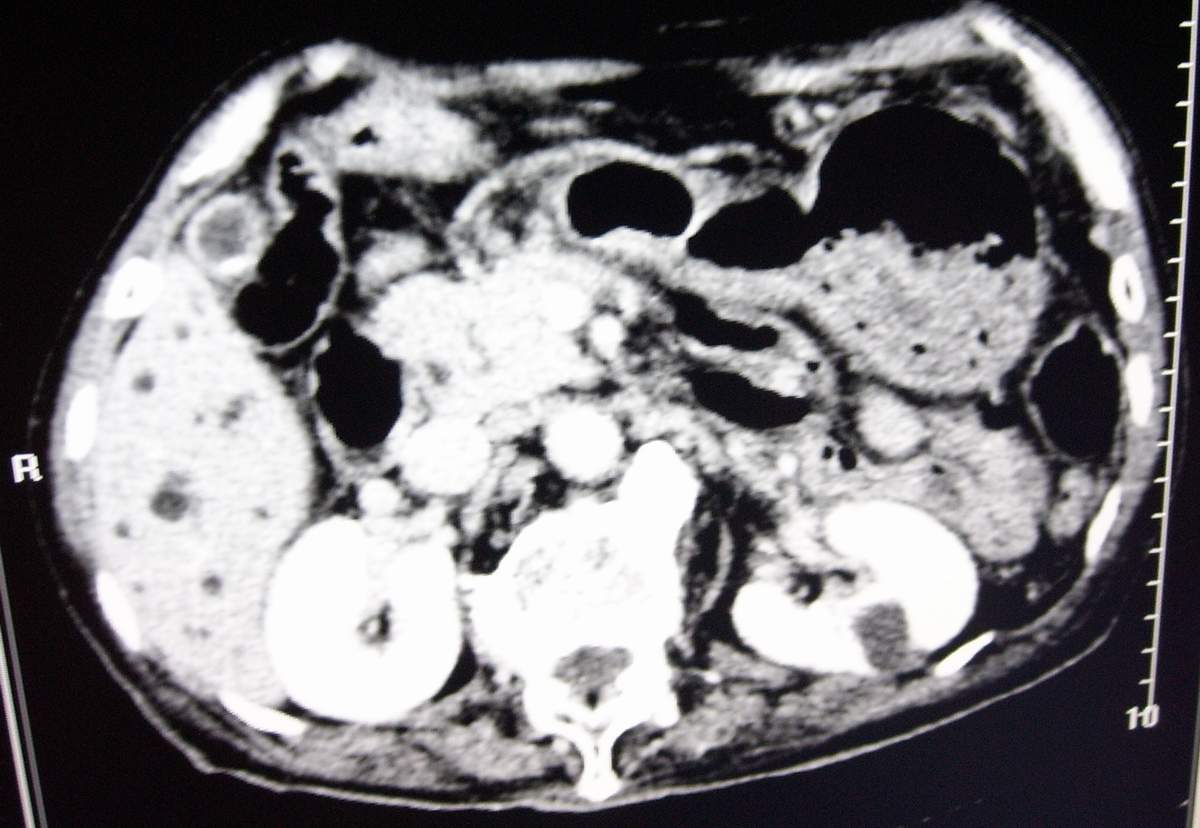

男,77岁,病史不详。

肝内外胆管明显扩张,肝门区见软组织密度肿块,胆囊壁增厚,胆囊扩大。胰头不大。考虑:肝门区胆管细胞癌。

考虑:1、华枝睾吸虫肝病(肝外胆管未见扩张,肝内胆管不成比例扩张,也就是失去分支规律的扩张,呈

外部呈柱状或囊状扩张,中部无明显扩张,而且边界不清);

2、胆囊结石、胆囊炎;

3、左肾小囊肿;

肝内胆管扩张明显,cbd未见明显扩张,胰管轻度扩张,肝门部胆总管癌?

肝内胆管普遍扩张,呈串珠状改变,走行不规则,且右叶胆管周围肝实质密度呈条片状减低,未见占位性病变,外周胆管及胰管扩张不及肝内胆管.胰腺钩突形态正常,胰十二指肠区域未见明显结节及肿块,初步考虑慢性胆管炎可能性大.请结合临床病史.另外用宽窗看一下吉氏筋膜有无增厚.

1肝门区域软组织影,肝内胆管明显扩张,胰管轻度扩张。考虑肝门区胆管细胞癌。2胆囊结石。3左肾小囊肿。

1 肝内外胆管扩张,肝内明显,胰管扩张,胰头明显增大,符合胰头癌双管征。2 胆囊壁略增厚,胆囊内可见高密度结石影,胆囊炎、胆结石3 左肾囊肿